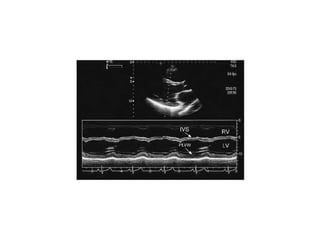

PLAX

Allows optimal recording of mitral leaflet excursion, mid left ventricular wall

motion, and visualization of a portion of the

right ventricle.

Allows optimal recordingof mitral leaflet excursion, mid left ventricular wall motion, and visualization of a portion of the right ventricle. The normal interventricular septal curvature can be appreciated and any abnormalities of septal position, shape, or motion can be assessed. Minor base-to-apex angulation is useful to record the orifice of the mitral valve, the coaptation of the leaflets, and the mitral chordae and their insertion into the anterolateral and posteromedial papillary muscles. In addition to the annulus, the aortic valve, coronary ostia, left atrium, interatrial septum, right atrium, tricuspid valve, right ventricular outflow tract, pulmonary valve, and proximal pulmonary artery can also be recorded.